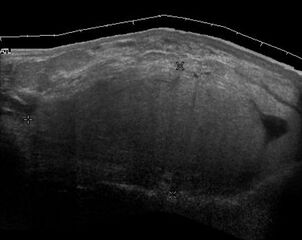

قد لا يكون التصوير بالموجات فوق الصوتية قادراً على التمييز بين الغرن الشحي والورم الشحمي الحميد، وبالتالي، فإن التصوير بالرنين المغناطيسي هو التصوير الأولي المفضل.[4]

Medical ultrasonography of a liposarcoma: In this case a heterogeneous mass consisting of an upper hyperechoic portion, corresponding to lipomatous matrix, and areas of hypoechogenicity corresponding to nonlipomatous components.[5]